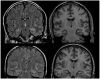

Results: Engel class I outcomes (free of disabling seizures) were observed in 60% (24 of 40) patients. Preoperative factors associated with Engel class I outcome were: (1) absence of contralateral or extratemporal interictal epileptiform discharges, (2) subtraction ictal single photon emission computed tomography (SPECT) Coregistered to MRI (SISCOM) abnormality localized to the resection site, and (3) subtle nonspecific MRI findings in the mesial temporal lobe concordant to the resection.

Figures